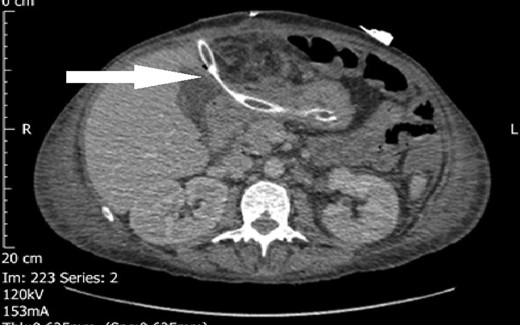

The decision to take the patient back to theatre was made on Day 16 for an emergency laparotomy for attempted partial gastrectomy and formation of a controlled fistula. The wound was found to have broken down at the level of the fascia with bowel prolapsing out with pus and gastric contents leaking through with the large abscess collection in Left Upper Quadrant and contaminated gastric contents throughout the upper abdomen. The duodenum was unable to be mobilized due to dense peritoneal inflammation and contamination. It was decided to pass a transgastric drain through the abdominal wall and into the non-healing defect in the distal stomach to produce a controlled fistula. A further drain was placed external to the stomach to protect against a leak (Figs 1 and 2).